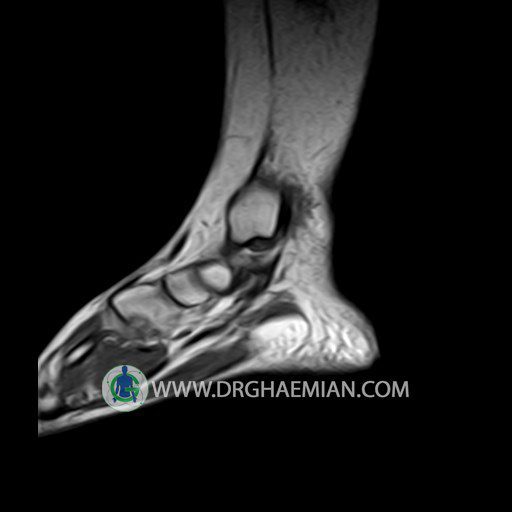

پزشکان اغلب از تصویربرداری ام آر آی برای تشخیص و درمان عارضه های پزشکی که فقط با استفاده از اشعه ایکس یا میدان مغناطیسی و امواج رادیویی قابل مشاهده است، استفاده می کنند. دستگاه ام آر آی تصاویر دقیق از ساختار های داخلی بدن ایجاد می کند. در این کیس تورم مچ پا بیمار مشاهده می شود.

Technique: Sagittal T1, T2 , Axial GE , coronal & sagital fatsat .